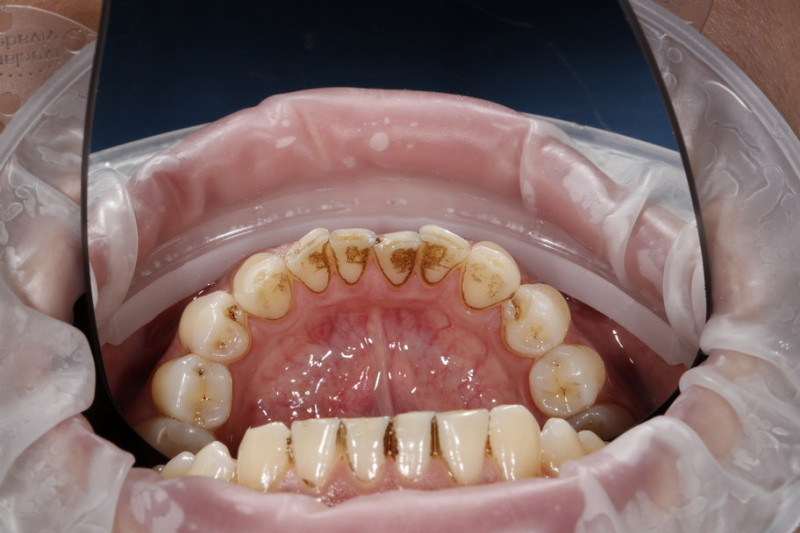

На странице представлено портфолио стоматологий Иркутска с работами до и после профессиональной чистки зубов. В нашем портфолио собраны разные клинические случаи: от удаления незначительного налета до снятия массивного поддесневого камня. Здесь вы можете увидеть, как возвращается естественный цвет и внешний вид зубов после процедуры. Изучите результаты до и после чистки зубов, чтобы увидеть реальный эффект и выбрать клинику в Иркутске, где профессиональная гигиена поможет вернуть зубам здоровый вид.

Комплексная профессиональная гигиена полости рта, врач Доржижапова Д.А. В нашей клинике чистка производится в четыре этапа: 1) Чистка ультразвуком (аппарат NSK, Япония) - убираем твердые отложения и зубной камень. 2) Обработка Air-Flow (NSK, Япония) - вода и специальный чистящий порошок подаются под давлением, вычищаем мягкий налет, пигментированный налет (от кофе, чая и сигарет), очищаем все поверхности зубов, включая межзубные промежутки. 3) Обработка щеткой и специальной полировочной пастой. Мы тщательно полируем зубы после чистки, что замедляет появление налёта в дальнейшем. 4) Ремтерапия и фторирование: В заключении в течение 1 минуты эмаль укрепляется каппой с гелем с различными вкусами. Гель снижает чувствительность зубов и насыщает их минералами.

Гигиена рта и очистка зубов происходит в три этапа: • Удаление камней с помощью ультразвукового скейлера. Ультразвук способен удалять налет не только на зубных поверхностях, но и в самых труднодоступных зонах, включая парадонтальные карманы. • Снятие зубного налета аппаратом Air Flow. Очищение зубов и пародонтальных карманов происходит за счет мощной водно-воздушной струи, насыщенную мелкими абразивными частицами. • Полировка зубов специальными инструментами и средствами, благодаря чему зубы приобретают естественный блеск идеальную гладкость.